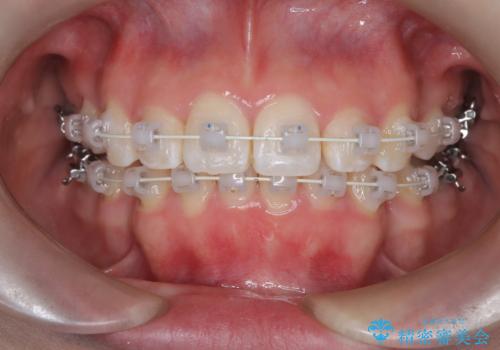

- 「歯のでこぼこと捻じれを治したい」を主訴に来院された患者様です。矯正検査の結果、上顎前歯がかなり唇側傾斜という結果になったので上下左右4番を抜歯をしワイヤー矯正で治療を行いました。

抜歯矯正でしたが順調に治療が進み2年で矯正治療を終えることが出来ました。歯のでこぼこや捻じれが治り、口元も下がって患者さんも大変満足されていました。